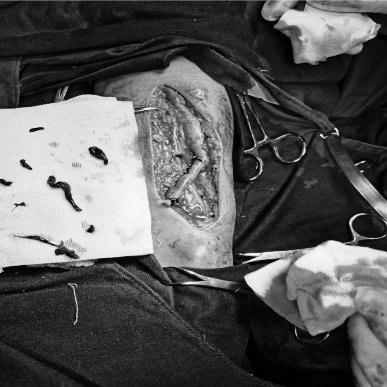

多年来,贵州航天医院各科室紧跟医学前沿,不断强技术、补短板,大力开展新技术、新项目,完成了许多高精尖、高难度、本地区“首例”的技术,填补了医院医疗技术空白,满足了群众日益增长的医疗需求。 本期,我们将为大家带来肾脏风湿科特色技术——动脉瘤、囊样扩张等切除+原位内瘘重建术。 案例分享 患者在6年前确诊尿毒症并开始进行血液透析,在入院前2天,发现右前臂出现包块,故前来我院肾内科就诊。在为患者完善了彩超等检查后,诊断为:慢性肾脏病5期,右前臂内瘘处动脉瘤形成,内瘘功能丧失。 考虑到患者曾行“冠心病+PCI术”,长期口服华法林治疗,监测凝血功能INR升高,手术中出血风险较大,在征得患者及其家属同意后,待其凝血功能INR正常后,为其实施动脉瘤切除+原位内瘘重建术。 因患者手术切口长、难度大,科室团队通过充气压脉带充气加压阻断血运,在右前臂距腕关节上约10cm处,沿动脉瘤皮肤表面纵行呈弧形切开2条长约9cm切口,内瘘吻合口静脉端见一30×20mm包块及多处小包块,经过认真,仔细的操作,最终成功为患者分离动脉瘤、脓性分泌物及坏死组织,并完成原位内瘘重建。术后,患者定期换药消毒,恢复良好。 开展动脉瘤、囊样扩张等切除+原位内瘘重建术,手术医生需经过相关专业培训,手术难度大,操作要求高。目前,贵州航天医院肾脏风湿科完全具备手术资质,已为遵义地区许多患者提供该项医疗服务,极大帮助患者节约了血管资源,减轻了因临时透析导管带来的痛苦及相关导管风险。 什么是动脉瘤、囊样扩张等 切除+原位内瘘重建术 自体动静脉内瘘是维持血液透析患者血管通路的首选方法,如果因为内瘘吻合口临近或穿刺部位形成血管瘤、囊样扩张,经过保守治疗效果不佳者,可采取动脉瘤、囊样扩张等切除,并重建动静脉内瘘。 动脉瘤、囊样扩张等切除+ 原位内瘘重建术原理 尿毒症患者动静脉内瘘术后,血液动力学的改变,经反复穿刺,导致内瘘吻合口临近或穿刺部位形成血管瘤或囊性扩张,严重时可出现动脉瘤破溃、感染等严重并发症,内瘘失功,对保守治疗效果不佳者,采取动脉瘤、囊样扩张等切除,并在原位重建动静脉内瘘。 动脉瘤、囊样扩张等切除+ 原位内瘘重建术优势 动脉瘤、囊样扩张等切除+原位内瘘重建,新内瘘成熟时间短,在短期内即可使用(约术后1周),大大提高了治疗成功率,并为患者节约血管资源。 血管通路是尿毒症维持性血液透析患者的生命线,而动脉内瘘是最重要也是最经济有效的血管通路。随着透析时间延长,部分患者内瘘血管出现动脉瘤,随时可能破裂大出血危及生命,内瘘也因此失去功能。此技术能解决内瘘动脉瘤所带来的危险,同时重建内瘘功能,对延长透析患者的生存时间,提高透析患者的生活质量具有重大意义。 贵州航天医院肾脏风湿科 专家团队 冯远军 肾脏风湿科主任 主任医师 临床擅长:对慢性肾脏病、急性肾损伤、急慢性肾小球肾炎、肾病综合症、风湿性疾病、间质性肾炎、肾小管损伤等疾病的诊治及血液透析技术、动静脉内瘘成形术及疑难病例的诊治具有丰富的临床经验。 曾在上海市第一人民医院及贵阳市第一人民医院进修学习,贵州省医学会肾脏病学分会第五届委员会委员,遵义市医学会肾脏病学分会第一届委员会副主任委员,遵义市医学会风湿病学分会第一届委员会副主任委员,荣获“贵州航天劳动模范、遵义市汇川区先进工作者”,遵义市医疗事故鉴定专家库成员,主持省市级科研项目4项,完成4项,近5年发表论文10余篇,北大核心期刊1篇。 王卫华 肾脏风湿科 主任医师 临床擅长:从事临床工作28年,擅长尿毒症患者血管通路的建设及维护(如标准和高位动静脉内瘘术、取栓+内瘘重建术、内瘘狭窄球囊扩张术、长期中心静脉置管术及肾穿刺活检术)等手术,对原发性和继发性肾病综合征、急、慢性肾小球肾炎、慢性肾脏病、泌尿系感染、结缔组织病、急性中毒、痛风、贫血、血小板减少症等疾病诊治及血液透析技术应用等具有丰富的临床经验。 1995年毕业于遵义医学院临床医学系,曾前往重庆医科大学进修学习肾脏疾病及血液净化;遵义市医学会肾脏病学分会常务委员,遵义市血液净化质量控制中心委员;先后发表肾病专业省部级医学刊物医学论文8篇,主持市级科研项目2项。 李丽华 肾脏风湿科 副主任医师 临床擅长:从事临床工作17年,对慢性肾脏病、急性肾损伤、急慢性肾小球肾炎、肾病综合征、风湿性疾病、间质性肾炎、肾小管损伤、急慢性肾衰竭的血液透析、CRRT治疗以及血管通路的建设维护等具有丰富的临床诊疗经验。 2006年毕业于遵义医学院临床专业,曾在遵义医学院附属医院完成住院医生规范化培养,并前往第三军医大学新桥医院、珠海市人民医院进修学习;中华医学会遵义市肾脏病学分会委员,遵义中医药学会肾病专业委员会委员,遵义市血液净化质量控制中心委员,遵义市医学会血液学分会委员会委员;发表省部级医学刊物医学论文4篇,主持参与省级科研课题1项,主持参与市级科研课题1项,院级新技术6项,获得本专业授权实用新型专利3项。 李 玫 肾脏风湿科 副主任医师 临床擅长:从事临床工作15年,对慢性肾脏病、急性肾损伤、急慢性肾小球肾炎、肾病综合征、风湿性疾病、间质性肾炎、肾小管损伤等疾病的诊治具有丰富的临床经验,擅长血液透析技术、动静脉内瘘成形术等。 2008年毕业于遵义医学院临床医学系,曾前往遵义医学院附属医院进修学习肾脏病与血液净化相关技术;遵义市医学会肾脏病学分会委员,发表肾病专业省部级医学刊物医学论文4篇。 贵州航天医院肾脏风湿科简介 贵州航天医院肾脏风湿科2017年建立,住院患者承载能力达到50人左右,透析治疗服务惠及250余人的患者群体,在学科建设、高端医疗设备引进及专业技术队伍已达到区域内领先水平。科室共有医护人员46名,副高级以上专家7名,亚专业设置齐全,涵盖肾脏疾病、风湿免疫疾病药物治疗、透析治疗及透析通路维护等多个专业领域,为患者提供全面、精准、高效的诊疗服务。配备了尖端的医疗设备与智能化的辅助系统,包括透析机、CRRT机等设备。 • ✦ 专科特色 ✦ • (一)肾脏病治疗领域:专精于血液透析、血液透析滤过、血液灌流、血浆置换、CRRT等尖端技术,致力于为患者量身打造个性化的肾脏替代治疗方案。 (二)在风湿病治疗方面:凭借生物制剂、免疫抑制剂等前沿药物,结合患者的具体情况,精心策划个体化的治疗策略,有效减轻患者症状,显著提升生活质量。 超声引导下球囊扩张术:内瘘狭窄是内瘘最常见的并发症之一,我们采用先进的超声引导下球囊扩张术,通过微创方式恢复内瘘通畅,有效避免了传统手术带来的创伤和痛苦。 内瘘血栓溶栓治疗、取栓术:血栓形成是内瘘功能丧失的主要原因之一,根据患者具体情况,采用溶栓治疗、取栓术等多种手段,确保患者及时恢复透析治疗。 内瘘动脉瘤形成治疗:动脉瘤是由于内瘘局部血流动力学改变引起的血管扩张性疾病,采取佩戴弹力绷带、手术修复等措施,防止动脉瘤进一步发展和破裂。 内瘘感染治疗:内瘘感染是内瘘并发症中最为严重的类型之一,一般采用敏感抗生素进行抗感染治疗,严重者采取手术清创等措施。 内瘘窃血综合征治疗:是由于内瘘建立后,远端肢体血流减少引起的一系列症状,通过调整透析方案、改善内瘘血流分布及必要时重建内瘘等措施,有效缓解患者的症状并提高其生活质量。 • ✦ 诊疗范围 ✦ • 擅长治疗急慢性肾炎、肾病综合征、肾衰竭等肾脏疾病;擅长治疗类风湿关节炎、系统性红斑狼疮、干燥综合征等风湿免疫性疾病,并为患者提供健康教育与康复指导,帮助患者更好地管理疾病,提高生活质量。